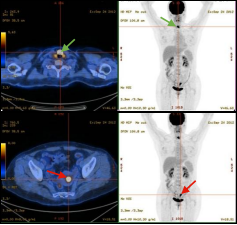

男,56岁,CEA: 40.5ng/ml,图A:肝脏多发转移瘤(红色箭头),图B:显示结肠肝曲高代谢肿块(绿色箭头),经肠镜证实为结肠腺癌。

右肺下叶肺癌伴阻塞性肺炎患者,CT难以精准指导穿刺,而PET/CT可准确区分肿瘤组织及炎性病变。绿色箭头示炎性组织,红色箭头示高代谢区域为肿瘤组织。